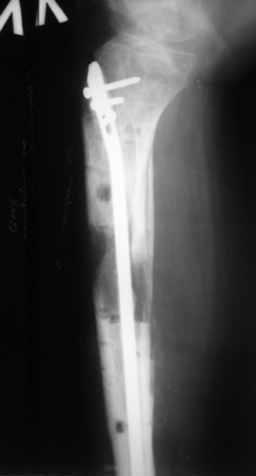

Ерсин, мы тоже имеем опыт такой фиксации. Подобную операцию за последние 3 года мы сделали трем пациентам. Снимки одного из них я прилагаю.

К сожалению, ни в одном из этих 3-х случаев мы не получили удовлетворяющего нас результата. Очень трудно провести штифт, введенный антеградно ровно по центру таранной кости. Отсутствие подвижности между диафизом и дистальным отломком большеберцовой кости (после фиксации в аппарате в течение 1-2 мес) очень усложняет проведение штифта в центр блока таранной кости. Поэтому мы от этого пока отказались, и проводим штифт через пятку. При данном варианте фиксации подобных проблем не возникало ни разу.